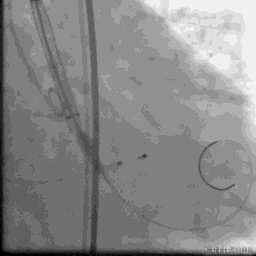

Numed20预扩

VenusA26定位

瓣膜释放三分之二

瓣膜完全释放